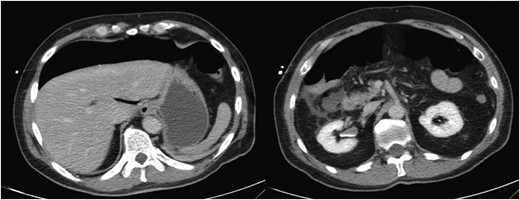

The patient presented to the emergency department 5h post-procedure complaining of abdominal pain and had a firm abdomen. He had a leukocytosis of 17 000. His Computerized Tomography (CT) scan showed a significant amount of pneumoperitoneum and inflammatory changes in the right lower quadrant in the region of the terminal ileum and cecum (Fig. 2). As the patient was improving, we initially attempted a trial of non-operative management. In the interim, pathology from the endoscopic biopsy had returned as extramedullary plasmacytoma. A baseline carcinoembryonic antigen level was 0.8. After ∼48 h the patient manifested signs of unsuccessful non-operative management characterized by increasing abdominal pain, tachycardia and rising leukocytosis. Therefore, we decided to perform an exploratory laparotomy.

Colonoscopic perforation on CT. CT scan of the abdomen revealing significant intra-abdominal free air (left). On a lower portion of the scan, there are inflammatory changes evident in the right lower quadrant in the region of the ileum and cecum (right). These structures are difficult to discern in the presence of the inflammatory changes.